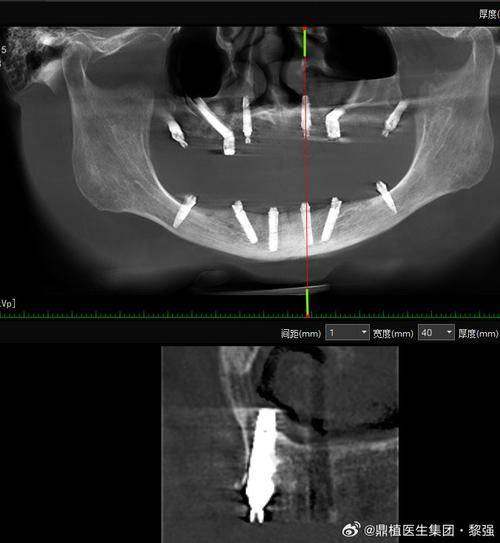

2. 必做准备:要做好全方面的口腔检查,包括X光片、CT等,让医生了解咱们的口腔情况,比如牙槽骨的密度、高度等,以便制定合适的种植方案。同时,要跟医生说清楚自己的病史和过敏史,比如是否有高血压、糖尿病等疾病,是否对某些药物过敏,这关系到手术的安心性。

1. 徐州口腔医院:徐州口腔医院开展多种种植牙技术,像常规种植、all - on - 4、all - on - 6等,技术较为全方面。收费6500元的种植牙在其收费区间内比较适中。虽然医生信息文档未提及,但作为当地有名的口腔医院,技术有一定的保护。而且医院开展的口腔治疗项目丰富,能为咱们提供一站式的口腔服务。

2. 徐州美奥口腔:这是一家正规私立连锁牙科,设有“MCIC复杂病例种植中 心”,擅长微创种植牙,种植体导航技术,all on four全口种植即刻负重,翼板区种植技术。医生团队有汪龙河、窦方伟、惠希琪等。韩国奥齿泰种植牙5500元起/颗,价格和徐州口腔医院6500元的种植牙有一定的可比性。这里种牙技术好,服务便捷,患者体验佳,是徐州牙科医院排名前十。

3. 徐州正博口腔医院:作为二级专科口腔医院,设立了无菌手术室,有着复杂病例种植中 心如穿颧穿翼种植、all - on - 4半口全口即刻种植技术。医生有王勇、李明等。韩国进口种植牙2980元起,韩国美格真种植牙4899元/颗等多种种植牙价格可供选择。以可靠医疗技术和优质服务在淮海经济地区享有较高声誉,设备高端,消毒严格,价格透明。